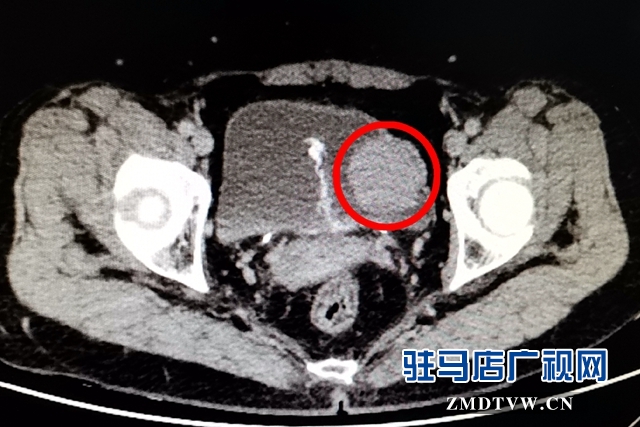

近日,張女士的“怪病”終于在駐馬店市中心醫(yī)院泌尿外二科治好了。原來,張女士的膀胱里長了一個雞蛋大小的腫瘤,叫嗜鉻細胞瘤,經(jīng)過手術(shù),切除了瘤體,張女士的血壓終于恢復(fù)正常了。

8月上旬,她在上蔡縣醫(yī)院做全身體檢時,竟發(fā)現(xiàn)膀胱有腫物,隨即來駐馬店市中心醫(yī)院泌尿外科就診。 據(jù)接診醫(yī)生黃雪強說:“入院后患者排尿時血壓高壓達到220mmHg,并且伴有頭暈、心慌、下腹不適的癥狀。泌尿系CT檢查,發(fā)現(xiàn)膀胱占位病變。”

經(jīng)過充分的術(shù)前準備,擴容,監(jiān)測控制血壓后,于8月24日在全麻下行膀胱部分切除術(shù)。手術(shù)中患者血壓波動劇烈,隨時有生命危險。主刀醫(yī)生文秀華、劉太陽憑借精湛的技術(shù),在麻醉醫(yī)師王震、手術(shù)室護士劉鵬、陳亞青等醫(yī)護人員的密切配合下,完整將膀胱內(nèi)直徑約5cm的瘤體切除。目前患者恢復(fù)良好,血壓完全恢復(fù)正常。